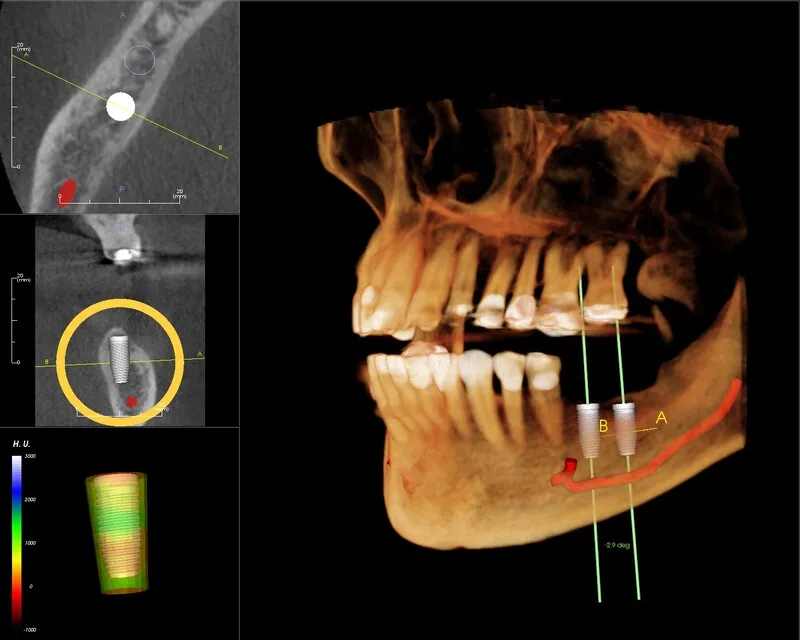

Chụp CT Conebeam là một công nghệ chụp cắt lớp vi tính sử dụng tia X, giúp tạo ra hình ảnh 3D chi tiết của các cấu

Chụp CT Conebeam là một công nghệ hiện đại, đặc biệt được ứng dụng rộng rãi trong các lĩnh vực nha khoa như chỉnh nha, cấy ghép